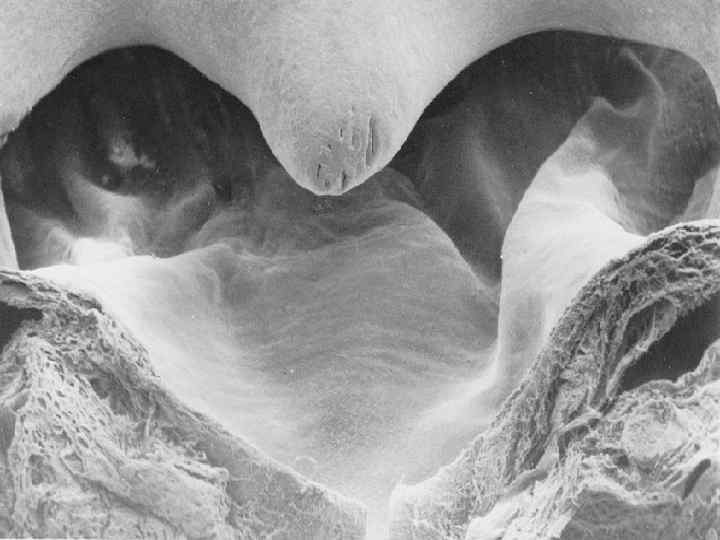

Фенестрированный эндотелий клубочкового капилляра

ПОЧЕЧНОЕ ТЕЛЬЦЕ (НА РАЗРЕЗЕ)

ПОДОЦИТЫ